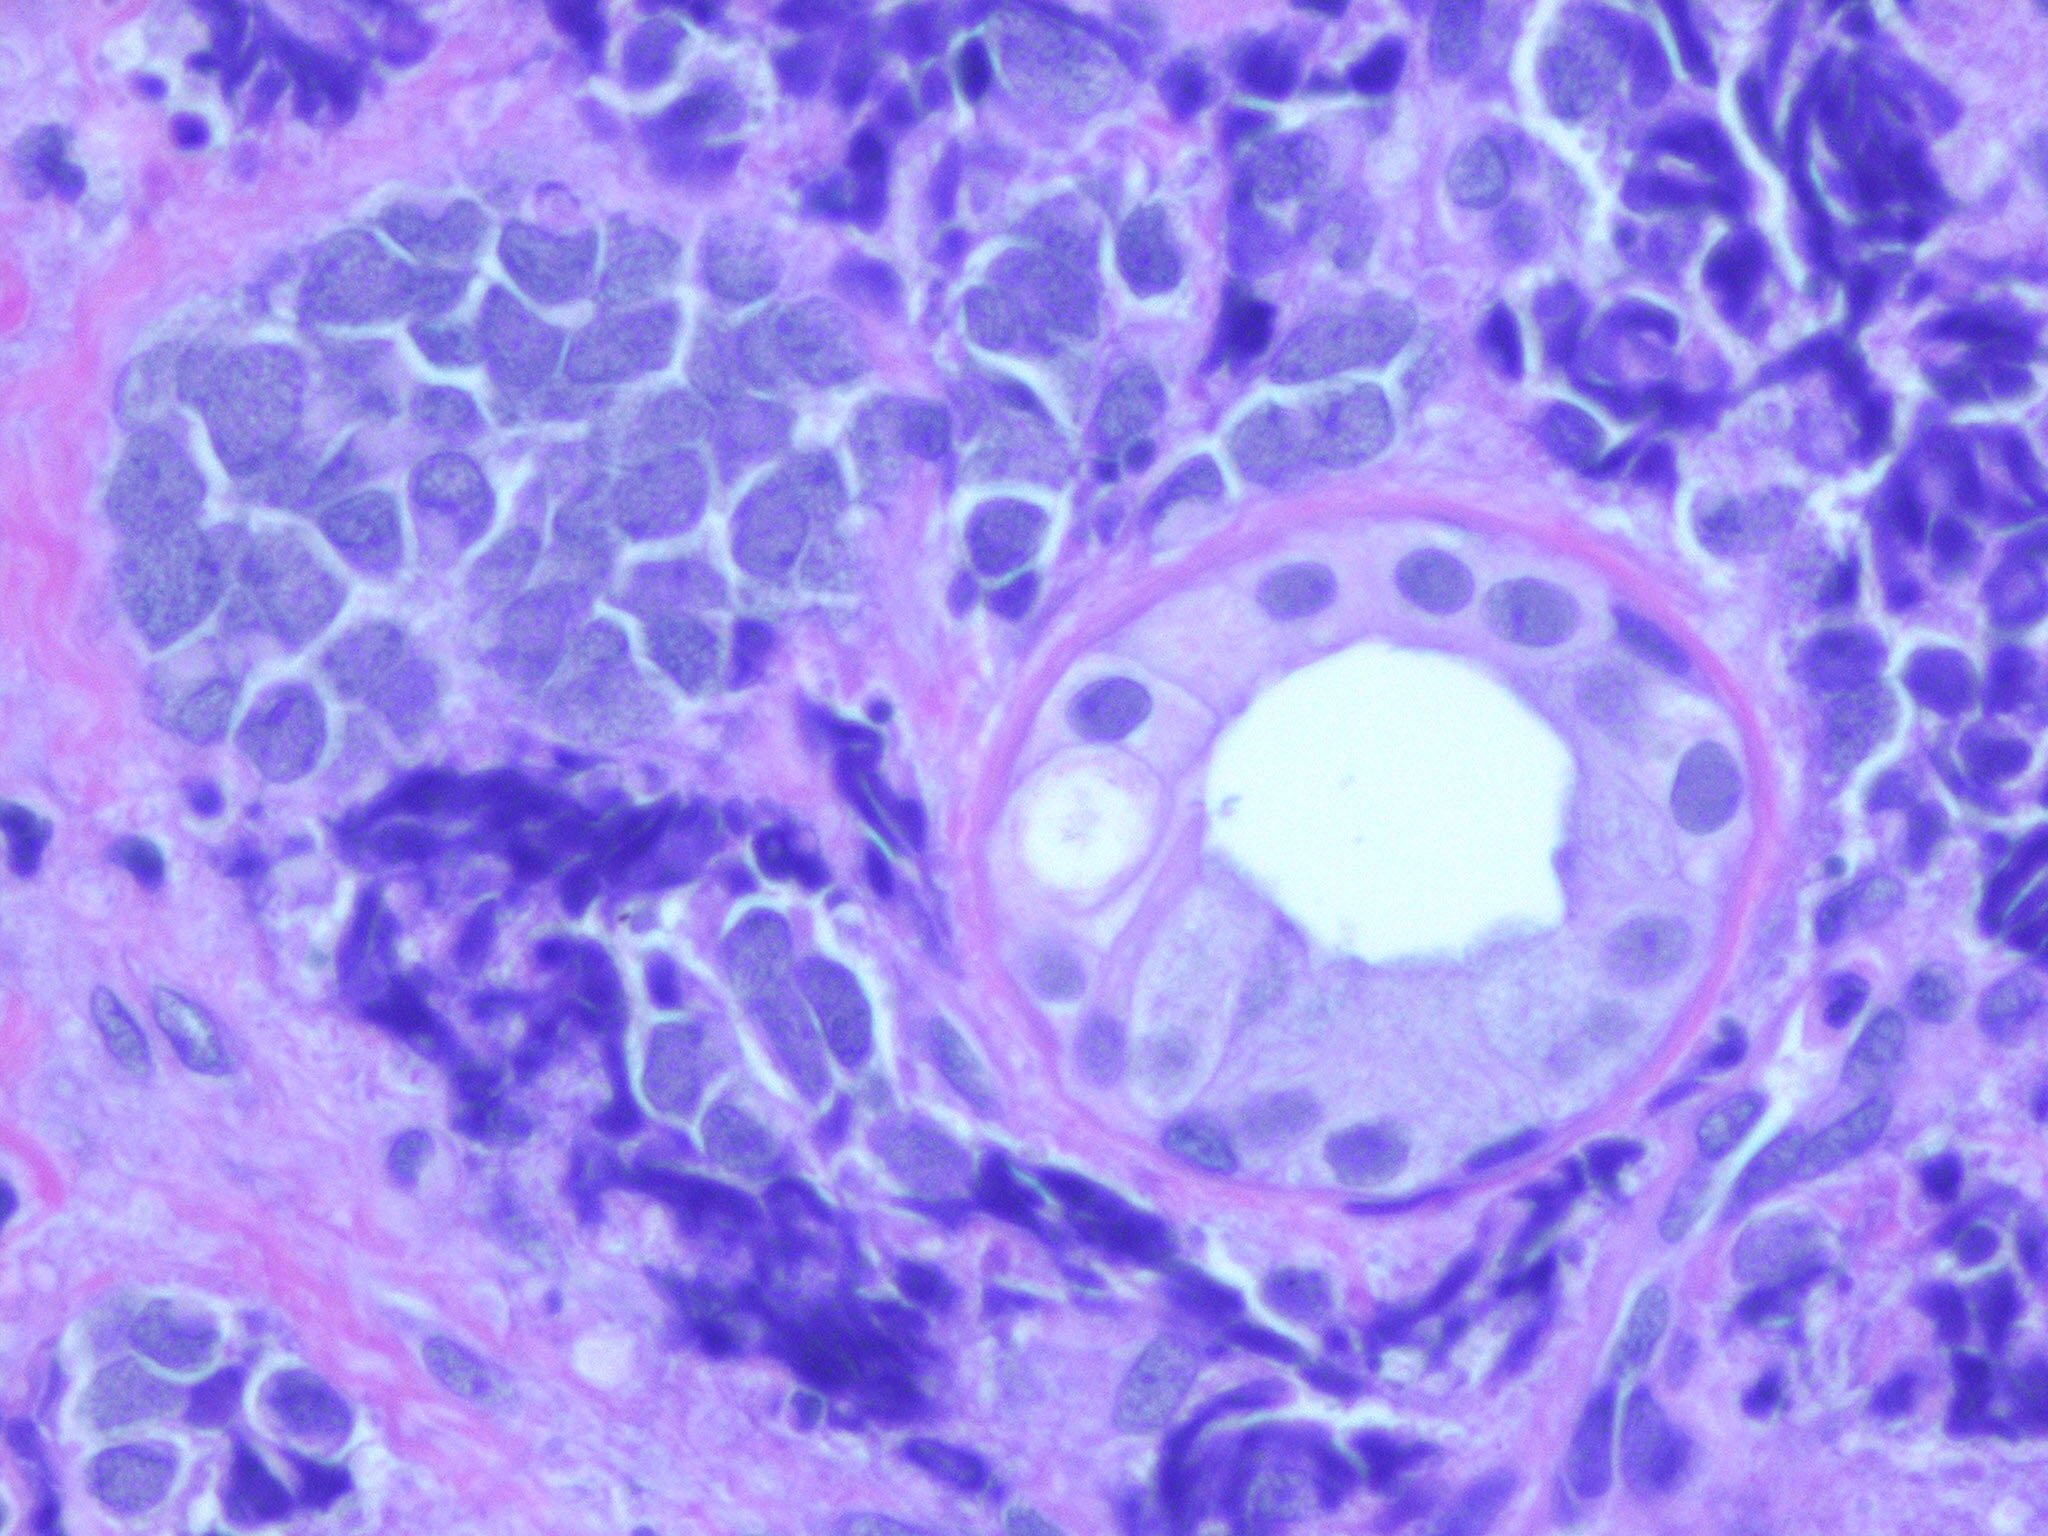

merkel-cell-carcinoma